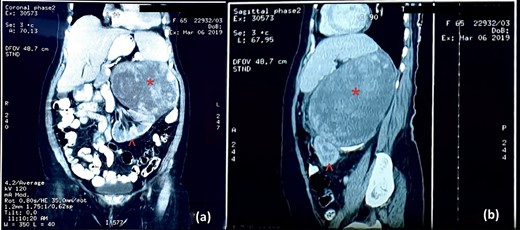

An abdominal ultrasound (US) revealed a 12 × 12 cm solid mass from the left suprarenal area (Fig. 1). Contrasted computed tomography (CT) revealed a 17.5 × 11.5 cm enhancing lesion in the left suprarenal region, completely replacing the left adrenal gland. The left kidney was inferiorly displaced, and coarse calcification was seen at the lesion’s periphery without lymph node enlargement. The contralateral adrenal gland, retroperitoneal and peritoneal structures were normal (Figs 2 and 3). Screening for primary carcinomas presenting as adrenal deposits utilizing clinical examination, pan endoscopy and contrasted CT were all negative. At this point, our working diagnosis was non-secreting left pheochromocytoma, and elective laparoscopic left adrenalectomy was planned.

CT image: (a) coronal section and (b) sagittal section; the red asterisk mark in (a, b) shows the tumour and the red arrowhead in (a, b) shows the inferiorly displaced left kidney.